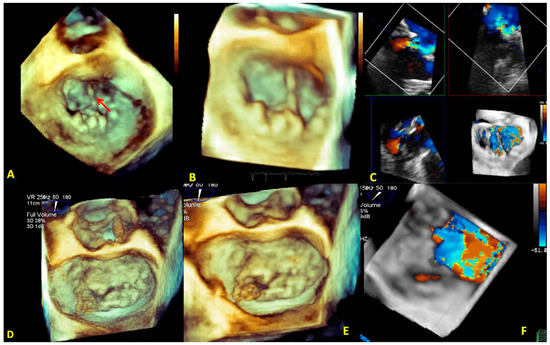

3.1. Anatomical Characterization

3.2. Quantification of the Morphology

3.3. Quantification of Mitral Regurgitation

3.4. Quantification of MV Stenosis